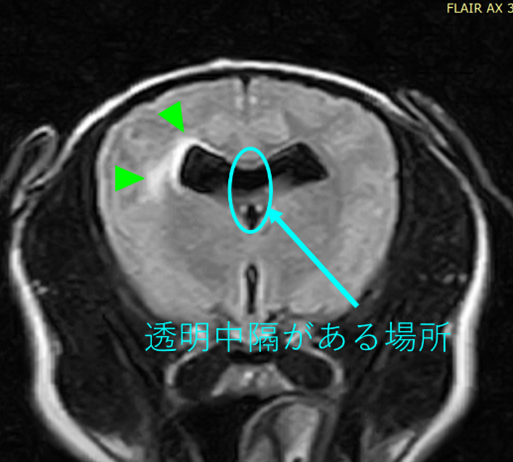

本症例のMRI検査所見:

・前頭葉白質領域(右>左)および右側大脳白質領域(側頭葉・後頭葉)にT2強調画像/FLAIR画像で高信号を示し、一部造影増強を示すびまん性の所見を認める。この所見は、DWI画像で高信号を示し、ADC-mapで大半は等~低信号を示す。

・透明中隔は欠損を疑うが、顕著な側脳室拡大を疑う所見は認められず、脳溝も明瞭である。